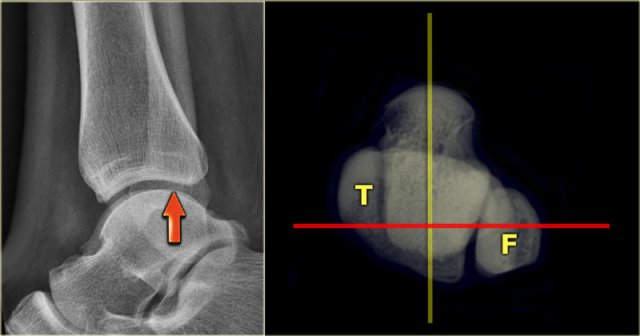

Mortise view

A basic radiographic examination of the injured ankle consists of an AP-view, a Mortise-view and a lateral view.

The Mortise-view is an AP-view taken with a 15-25? endorotation of the foot.

The technologist turns the foot inwards until the lateral malleolus is at the same height as the medial malleolus.

This view visualizes both the lateral and medial joint spaces.

On a true AP-view the talus overlaps a portion of the lateral malleolus, obscuring the lateral aspect of the ankle joint.

The distal fibula should project on the posterior part of the distal tibia The distal fibula should project on the posterior part of the distal tibia

Lateral view

Many think that for a good lateral view the distal fibula should be in the center of the distal tibia.

However, since the fibula is positioned more dorsally, the fibula should project over the posterior part of the distal tibia (arrow).